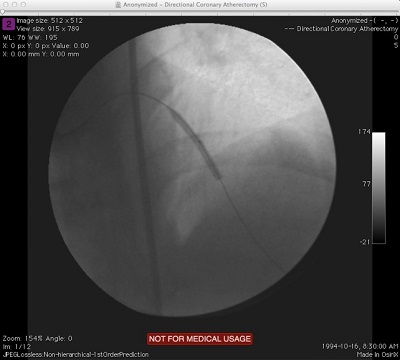

Extracting Image Data to Files (Multi-Frame)

When the convertFileToEightBitImage method is invoked on multi-frame DICOM files, the output file names will be postfixed with the frame number before the format extension. So, for a DICOM file containing two frames of image data for instance, specifying "output.jpg" for the output file name will result in two jpg files "output_001.jpg" and "output_002.jpg" created in the output directory. Code illustration is show below. There are a number of other overloads for the convertFileToEightBitImage method as well as other methods in the ConsumerFormatImageMaker class which provide access to the individual frames of a multi-frame DICOM file if we needed them. I will leave it to you to explore them.

String dicomFile = "D:\\JavaProjects\\Sample Images\\XA-MONO2-8-12x-catheter";